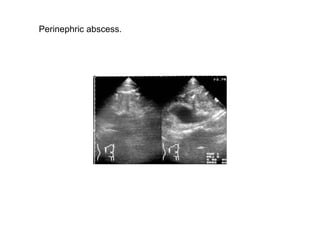

Perinephric abscess.